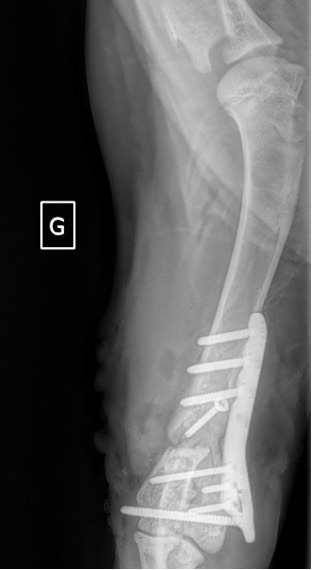

Exemple 2 :

Figure 6 : Post-Op 1 mois

Figure 7 : Post-Op 2 mois